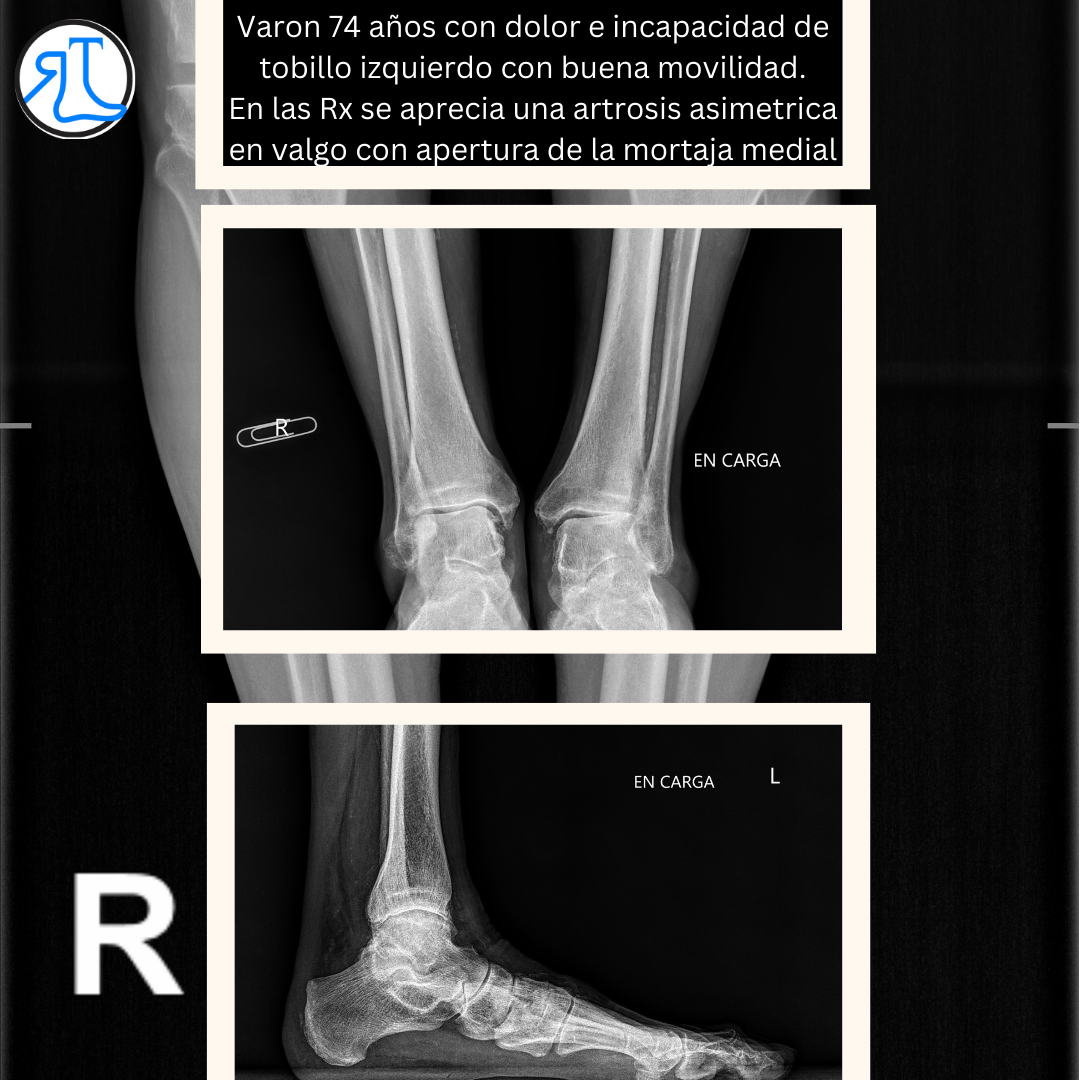

El paciente era muy reacio a perder la movilidad de su tobillo (muy conservada) por lo que se decidió implantar una prótesis de tobillo junto con una reconstrucción de ligamento deltoideo mediante el uso de un aloinjerto.

El tipo de prótesis implantada obliga a una inmovilización en el postoperatorio inmediato pero pese a ello el paciente ha recuperado una movilidad no dolorosa que le permite desarrollar una actividad plena.